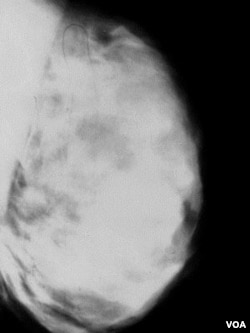

Hasil mammografi payudara yang mengandung banyak sel lemak.

Perempuan yang menjalani mamografi setiap dua tahun, beresiko lebih kecil mendapat misdiagnosis kanker payudara dibanding mereka yang diperiksa setiap tahun

Pada tahun 2009, U.S. Preventive Services Task Force, komisi pemerintah yang terdiri dari para pakar, merekomendasikan mammografi kanker payudara setiap dua tahun sekali, mulai usia 50 tahun. Standar sebelumnya adalah satu tahun sekali, mulai usia 40 tahun. Perubahan tersebut menuai kontroversi, dan banyak perempuan serta dokter mereka masih mengikuti rekomendasi yang lama.

Dalam studi terbaru, Diana Miglioretti dari Group Health Research Institute di Seattle dan koleganya meneliti catatan kesehatan sekitar 170.000 perempuan yang menjalani mammografi. Mereka mendapati bahwa sebagian besar perempuan yang melakukan pemeriksaan setiap tahun memiliki hasil positif yang keliru.

"Kami mendapati bahwa lebih separuh dari jumlah perempuan tersebut, setelah 10 tahun menjalani pemeriksaan tahunan, akan diminta untuk melakukan pencitraan selanjutnya, dan hasilnya mereka tidak berkanker. Dan tujuh persen dari perempuan tersebut akan disarankan menjalani biopsi yang hasilnya tidak menunjukkan kanker," tutur Dr. Miglioretti.

Temuan lain dalam studi tersebut menunjukkan bahwa perempuan yang menjalani mammografi setiap dua tahun sekali hanya bertambah sedikit kemungkinannya terkena kanker. "Kami menemukan peningkatan yang sangat kecil dalam kemungkinan menderita kanker payudara stadium akhir pada perempuan yang diperiksa setiap dua tahun, tapi secara statistik tidak signifikan," tambahnya.